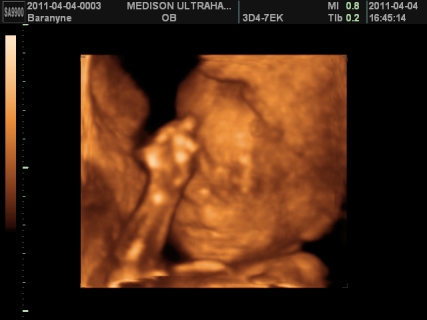

gyerek témában is helyretettem magam, ennek is tök egyszerű oka van, FÉLEK TŐLE. ezen nem változtat az idő, ha 1 év mulva mennék ,akkor is félnék tőle. sajnos nekem nem életem legszebb élménye volt a várandóság, én tényleg terhességként éltem meg. egyszerűen annyi a szabadságomnak, mert szinte mindenről le kell mondanom, bár remélem most nem így lesz meg. ámulva hallgatom, akinek a legszebb élmény a várandóság volt. valamilyen szinten nekem is, de csak mikor kiderült ,hogy sikerült és mikor megszületett boti, a többi rész kihagynám, mert nem tudtam önfeledten örülni sem az első szívhangnak, sem az első uh-nak, mert mindig bennem volt a félsz. ezt talán legjobban bibó értheti meg. viszont nagyon nagyon szeretnék egy kismanót, de egyszerűen nem tudom elképzelni, hogy hogy fogom tudni boti mellett megoldani. anyuékhoz sem passzolhatom le mindig botit, ha mondjuk fáradt leszek, vagy isten ne adja vérzek. mi lesz vele? na ezen ráérek agyalni, de már nem sokáig, mert kb 3 hét és visszaülti. bár tudnék felhőtlenül örülni, de a félelmemet nem tudom leküzdeni. alig várom ,hogy jöjjön a kisboti